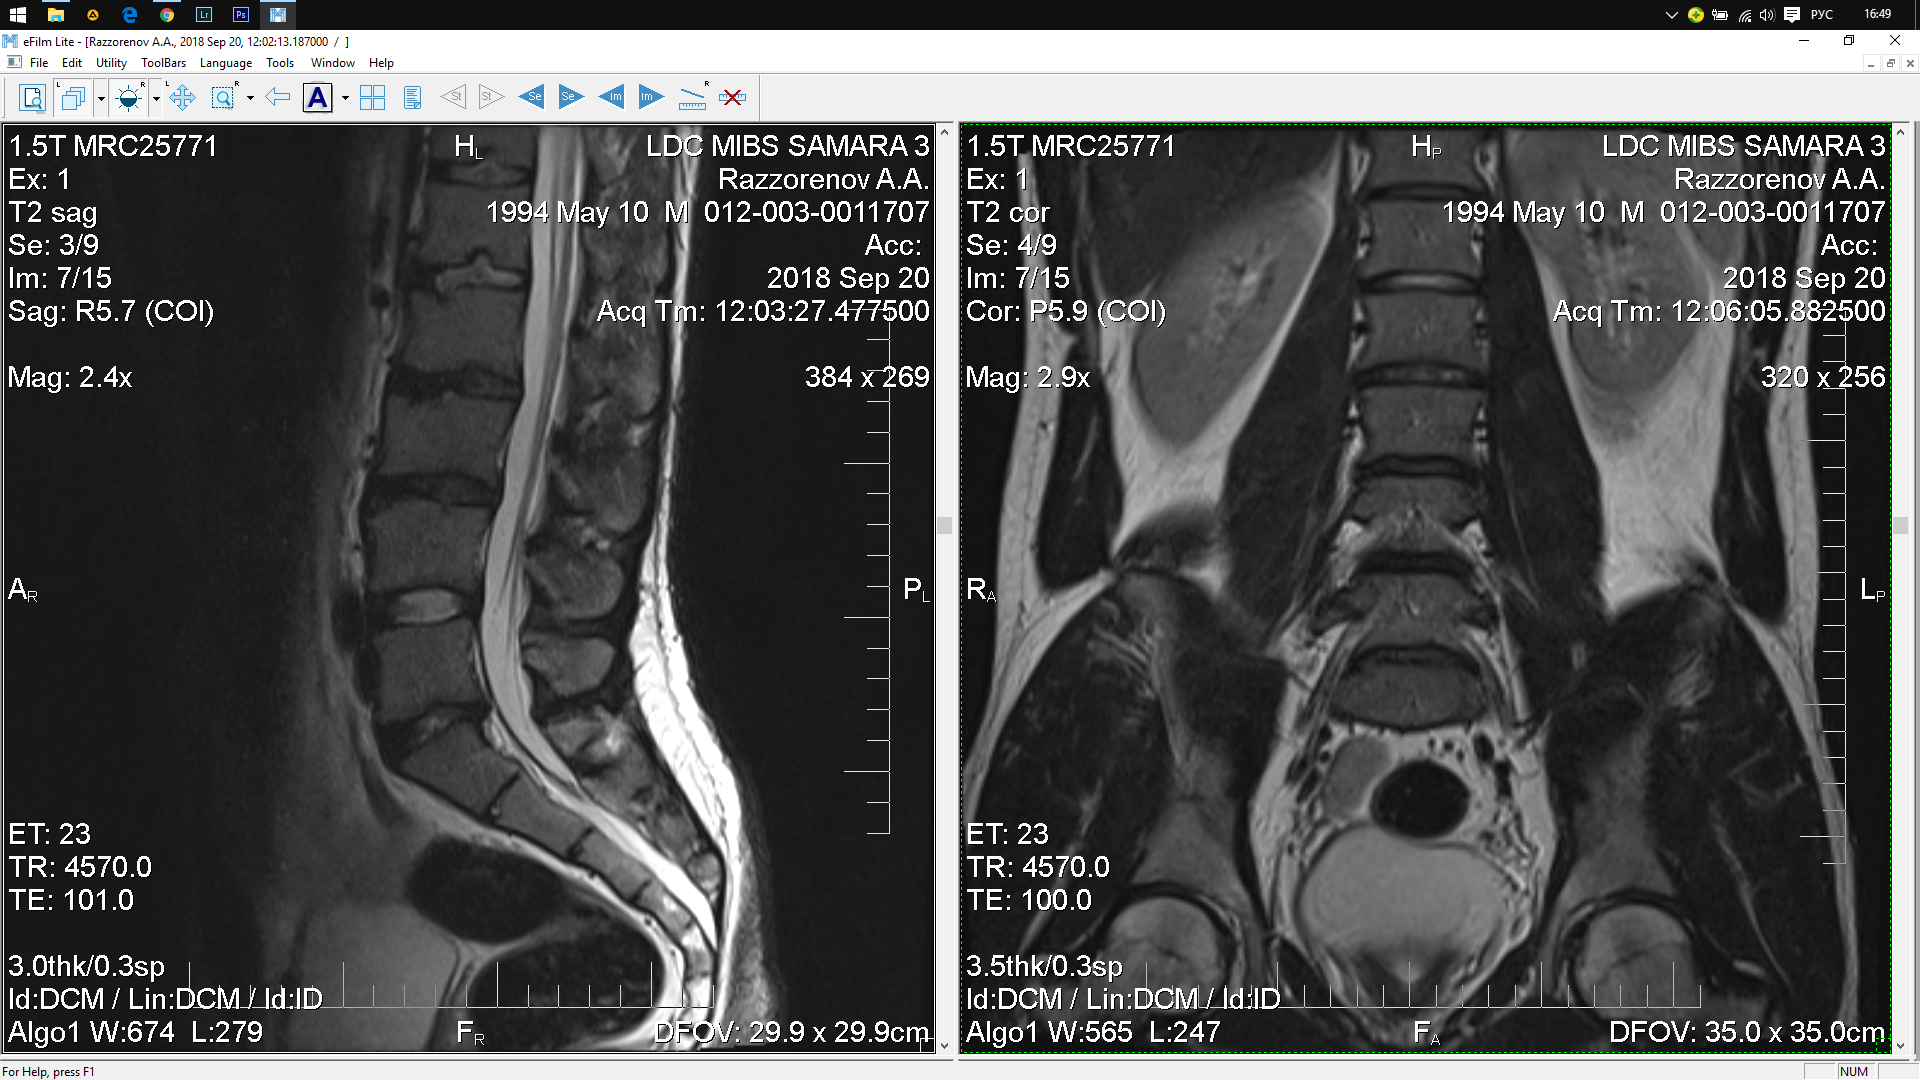

Тренировки с межпозвоночной грыжей.